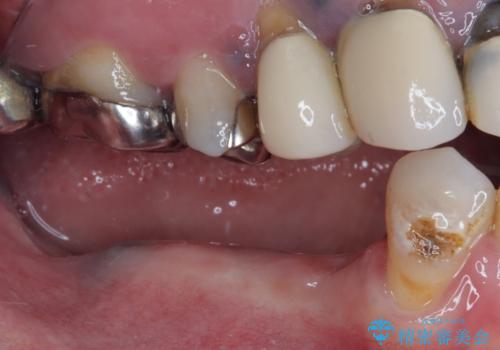

- ブリッジが装着されている奥歯がぐらぐらするとのことで来院された患者様です。

診察を行ったところ、手前の歯は歯根が破折しており、抜歯が必要な状態でした。

左右ともに臼歯部しか咬んでおらず、ブリッジの手前側の歯が破折したことで大きく揺さぶられてしまい、奥側の歯も周辺の歯が著しく吸収し、抜歯が必要な状態でした。

ブリッジの支台歯2本を抜歯し、反対側の咬合負担を軽減するために、通常よりも短い待機時間で2本のインプラントを埋入することとしました。

インプラントは、根管治療をした歯と比べると、破折するリスクは圧倒的に低いですが、こちらの方のように、臼歯しか咬合していない場合、歯ぎしりによる負担でインプラント周辺の骨が吸収する可能性があります。

就寝時のマウスピースの装着と定期的な通院によるレントゲン撮影や咬み合わせのチェックが必須となります。